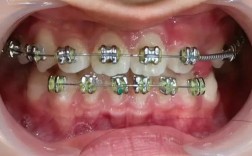

正畸后TMD的发生并非偶然,多与多种因素相关,咬合改变是核心原因之一,正畸过程中牙齿移动、颌骨位置调整可能暂时打破原有的咬合平衡,若新建立的咬合关系与关节肌肉功能不匹配,关节负荷异常,易引发紊乱,后牙咬合过浅可能导致咀嚼肌过度发力,而个别牙早接触则可能使关节受力集中,治疗设计不当也可能增加风险,如未充分考虑患者的关节适应性、强行矫正颌骨关系、或拔牙设计不合理导致咬合支点改变等,个体易感性不可忽视,部分患者本身存在关节结构异常、肌肉紧张或精神压力(如焦虑、紧咬牙习惯),正畸治疗可能成为诱发因素,治疗过程中若施加过大的矫治力或治疗时间过长,也可能加重关节负担,导致症状出现。

预防正畸后TMD的关键在于规范治疗和全程监控,正畸前需进行全面评估,包括关节触诊、咬合分析、必要时拍摄关节X线片或进行磁共振检查,排除潜在关节问题,治疗中应遵循“轻力矫治”原则,避免急功近利,定期复查调整方案,确保牙齿移动与肌肉、关节协调适应,对于存在TMD倾向的患者,可设计分阶段治疗,先通过咬合板或肌肉训练稳定关节,再进行牙齿矫正,治疗后需注意咬合适应,避免过早进食过硬食物,同时纠正不良习惯(如单侧咀嚼、托腮)。